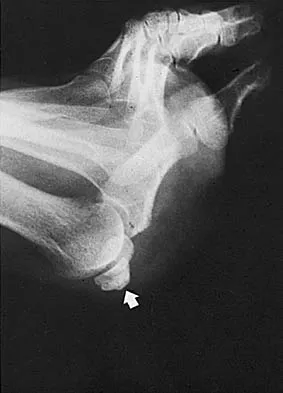

Figure 1 shows the radiograph of an 11-year-old boy who stubbed his great toe while playing soccer barefoot. He is able to walk home despite a small amount of bleeding at the nail fold. Management should consist of

Explanation

Great toe fractures through the physis should be considered open fractures if there is bleeding at the nail fold. Treatment should include irrigation and debridement and appropriate antibiotics. Immobilization with a cast is usually sufficient for treatment of the fracture. Noonan KJ, Saltzman CL, Dietz FR: Open physeal fractures of the distal phalanx of the great toe: A case report. J Bone Joint Surg Am 1994;76:122-125.